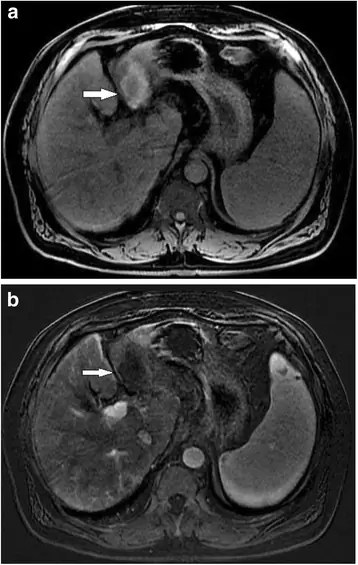

Внутриклеточный липид, обнаруженный в узле при двойном эхо в и противофазной МРТ, взвешенной по фазе T1, является дополнительным открытием, которое, как было показано, является достаточно специфичным для ГЦК. Это может быть полезным дополнением к набору инструментов при рассмотрении поражения с неспецифическими характеристиками усиления, поскольку внутриклеточный липид очень редко встречается в регенеративных или диспластических узлах (51) (рис. 3).

Рисунок 3

71-летний мужчина с циррозом гепатита С. Сигнал выпадает на противоположной фазе изображения (б) по сравнению с в фазе изображения (а). Результаты представляют внутриклеточный липид в опухоли ГЦК

Изображение в полном размере